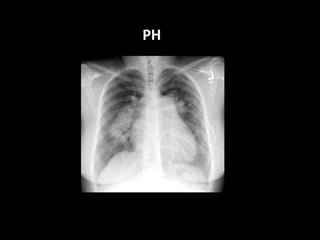

PH